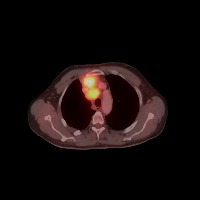

Diagnostic Aid in Medical Imaging: Radiologists could use this model to identify and characterize lymph node tumors in CT scans, assisting in early detection and diagnosis of potential cancerous growths.

Medical Research: Researchers might employ the model to study the characteristics and progressions of various types of lymph node tumors, towards producing more effective treatments and prevention strategies.

Training Medical Students: This model could serve as an invaluable tool for training medical students or residents in radiology, allowing them to familiarize themselves with the appearance and location of different lymph nodes, as well as to recognize varied tumor classifications.

Telemedicine: In remote or rural areas lacking immediate access to expert radiologists, this model can come handy as it assists primary care providers or mid-level practitioners in identifying lymph node tumors and making more effective referrals.

Second Opinion: Patients with possible lymph node tumors might use the model as a 'second opinion' to verify diagnoses, ensuring there are no oversights in their scans.